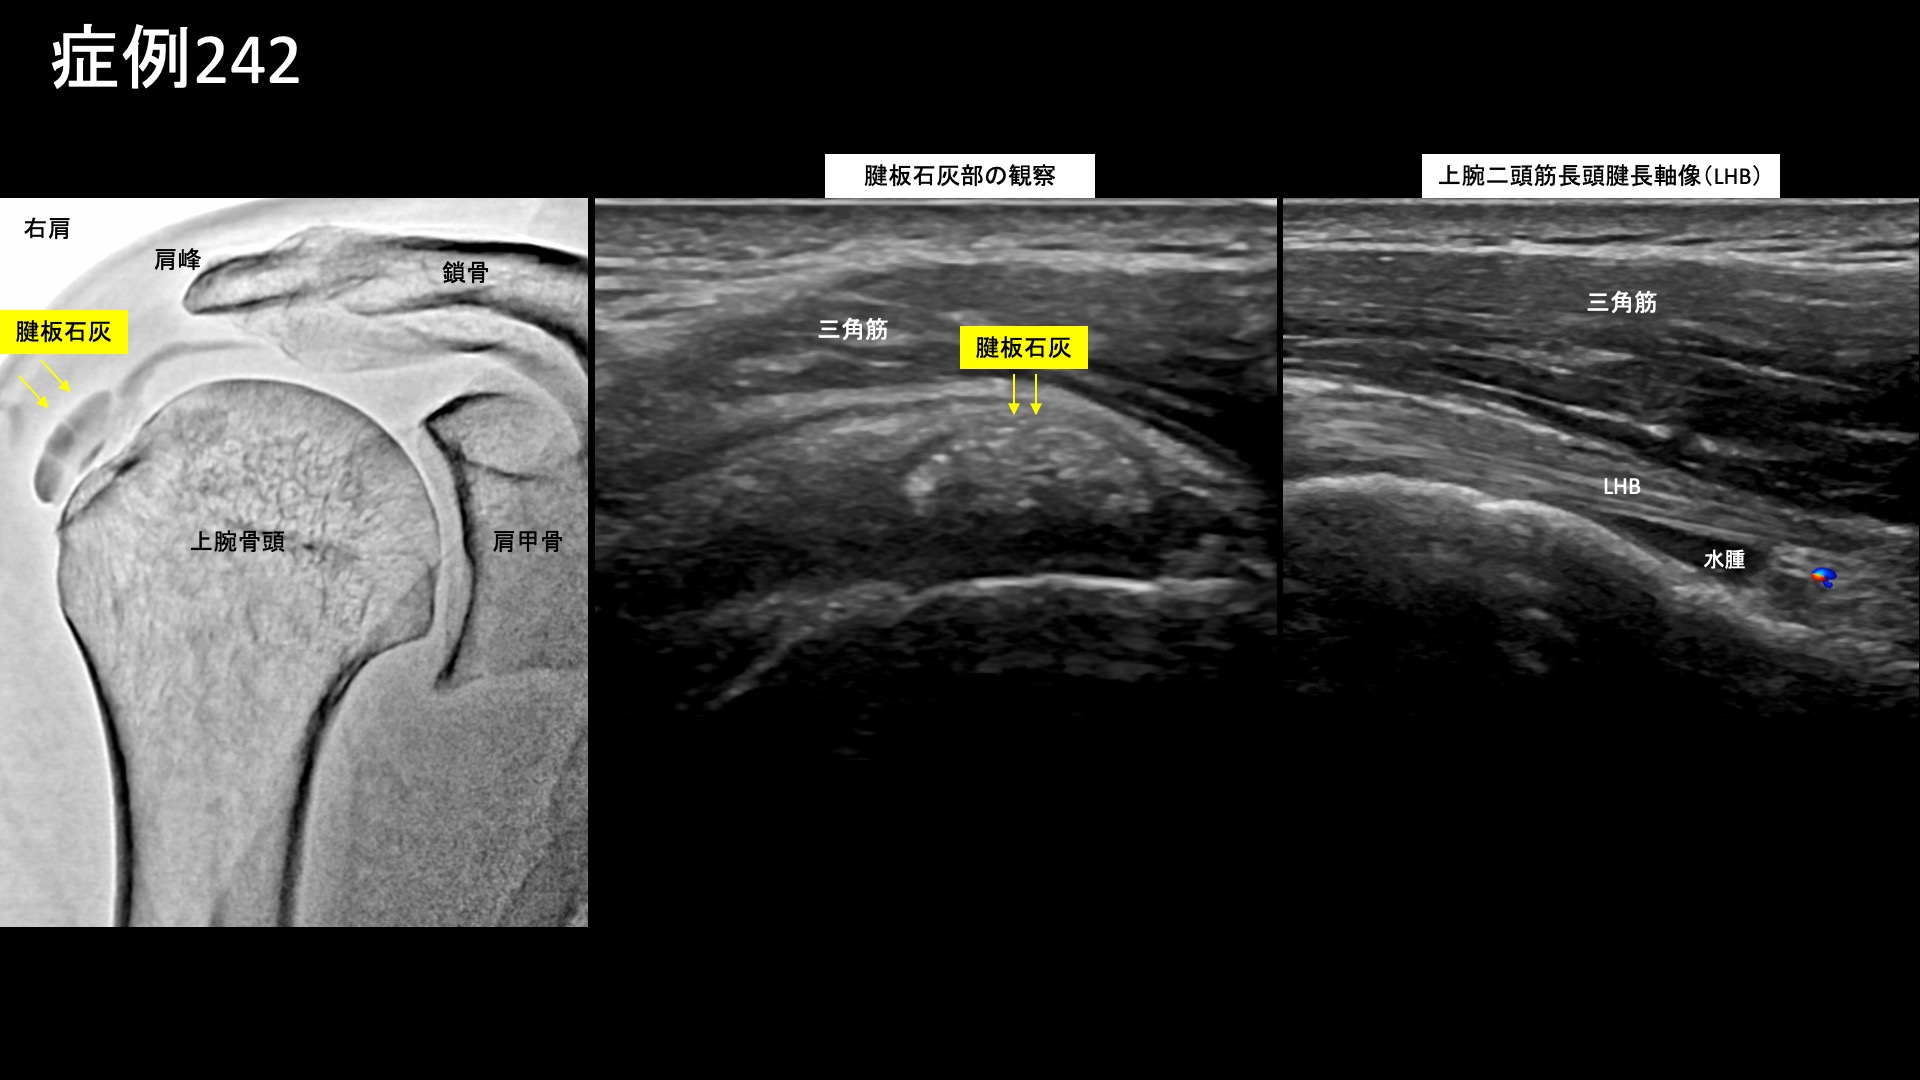

肩:肩こり・四十肩・五十肩 【50代:男性】真っすぐに座ると首から腕に激痛が・・車の運転がつらい・・重症首肩こりに対するモヤモヤ血管治療(首肩こり、頸椎症性神経根症) 2025.10.09 鴨井院長による動画解説 受診までの経過 3年前から首に違和感がありました。4ヶ月前に左肩に強烈な痛みが走り、レントゲン検査・MRI検査を受けたところ、症状の無い右肩も含めて両肩腱板に石灰沈着を認め、石灰沈着性腱板炎およびストレートネックと言われました。リハビリの方針となりましたが、効果を感じられず通院を止めていました。その後、1ヶ月前頃からは異なる症状が出てきて、背骨が真っ直ぐになるような姿勢をとると首~左肩~左腕にかけて痛むようになりました。特に椅子に座ると顕著であり、車の運転が日常的に苦痛となりました。治療方法を求めて当院を受診されました。 診察時の所見 症状の性状からは、肩関節周囲炎ではなく、頸椎症性神経根症や、重症の首肩こりである頸肩腕症候群などが疑われました。やはり、両肩関節の可動域は問題ありませんでした。一定の動作時時は見られました。首の可動域は中等度制限されており、特に後屈ではより顕著でした。レントゲンでは、頸椎は比較的保たれていました。肩関節では右側で腱板領域に粗大石灰を、左側でも少量の石灰沈着が見られました。しかしながら、エコー検査ではこれらの石灰沈着部周囲には炎症所見は見られず、陳旧性のものであることが示唆されました。一方、上腕二頭筋長頭腱周囲には水腫が見られるなど一定の炎症所見が認められました。また、棘上筋腱の部分断裂も認められました。以上より、首肩こり、および軽度の両側肩関節周囲炎(有痛性腱板損傷および、石灰沈着性腱板炎後遺症)と診断しました。治療適応と判断し、モヤモヤ血管(病的新生血管)に対する運動器カテーテル治療(微細動脈塞栓術)を受けていただきました。 治療の所見 血管造影を行うと、やはり肩関節のモヤモヤ血管よりも頸部のモヤモヤ血管の方が目立っていました。特に左頸部における深頸動脈造影においてモヤモヤ血管が濃染像として描出されました。治療後は画像上速やかに消失しました。その他複数箇所の治療を行い終了しました。 治療後の経過 治療当日から改善し、治療後2週間では、ほとんど痛みが気にならなくなりました。首を動かした際に時折つんとするような痛みが出る程度でした。よく眠れるようにもなりました。『正直半信半疑だったが、良くなってうれしい』と言われました。その後、痛みではないものの首から肩にかけてずーんと感じることはありましたが、治療後2ヶ月半になると痛み・こりともほぼ消失しました。運動習慣も取り入れていただき、様子を見ることとしました。その後も左頸部~肩の症状はぶり返すことなく順調に経過されています。尚、腱板石灰についてはやはり陳旧性のものであり、症状改善後も残存していました。新鮮なものではないため、自然吸収は期待できませんが、残存していても痛みなく過ごせる方は多いです。本症例は、頸部由来の上肢に至る神経症状をきたしている状態でした。頸椎症性脊髄症については治療効果に限界がありますが、神経根症までの段階、あるいは筋・筋膜・血行などに起因するいわゆる重症の首肩こりであれば、モヤモヤ血管に対する運動器カテーテル治療が非常に有効です。治療後は、痛みの改善だけでなく、よく眠れるようになった、眠りが深くなった、身体が軽くなったなどの感想をいただくことが多いです。首肩の不調は全身の不調につながりますので、お悩みの方はぜひご検討いただくとよいと思います。 首こりの詳細はこちら 【80代:男性】火が出るような痛みに襲われ夜も寝られず・・発症1ヶ月の頭部/顔面に生じた帯状疱疹後神経痛(帯状疱疹後神経痛) 前の記事 【50代:男性】ヘルニアによる腰部神経根症が原因の腰臀部痛に対して、減量とカテーテル治療を行い完治した症例(腰椎椎間板ヘルニア、椎間孔狭窄、神経根症、減量/マンジャロ) 次の記事